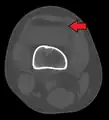

In all injuries to the tibial plateau radiographs (commonly called x-rays) are imperative. Computed tomography scans are not always necessary but are sometimes critical for evaluating degree of fracture and determining a treatment plan that would not be possible with plain radiographs.[5] Magnetic Resonance images are the diagnostic modality of choice when meniscal, ligamentous and soft tissue injuries are suspected.[6][7] CT angiography should be considered if there is alteration of the distal pulses or concern about arterial injury.